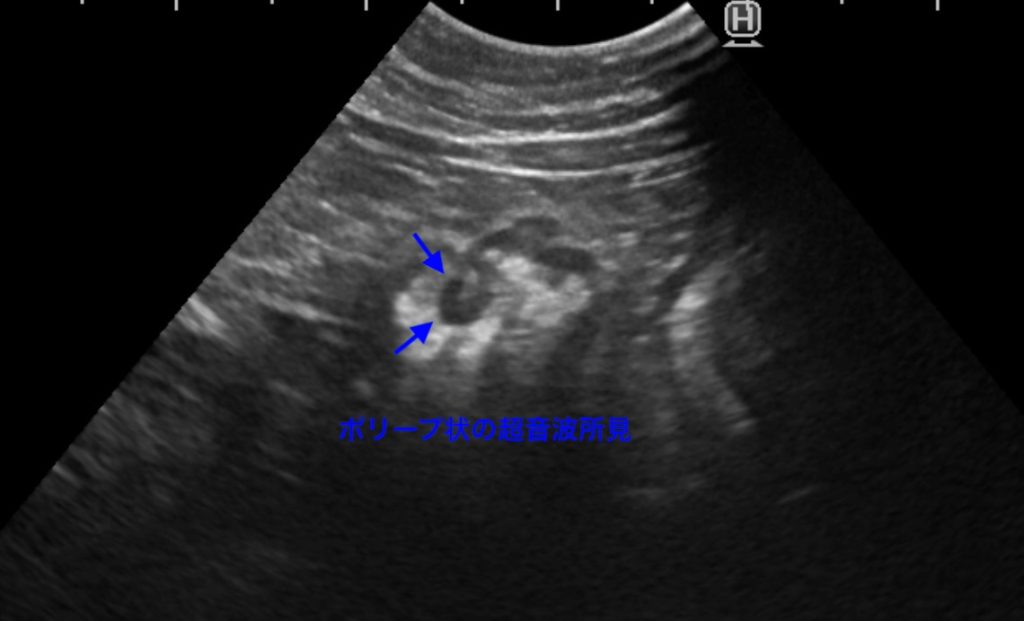

胃の粘膜が肥厚し、一部にポリープ状のものが認められました。